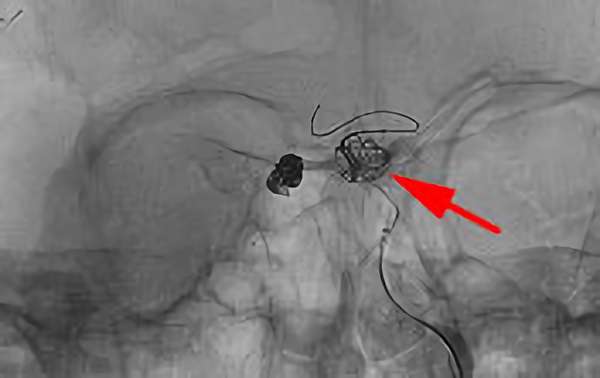

No.1628 手術前

No.1628 手術中

No.1628 手術後